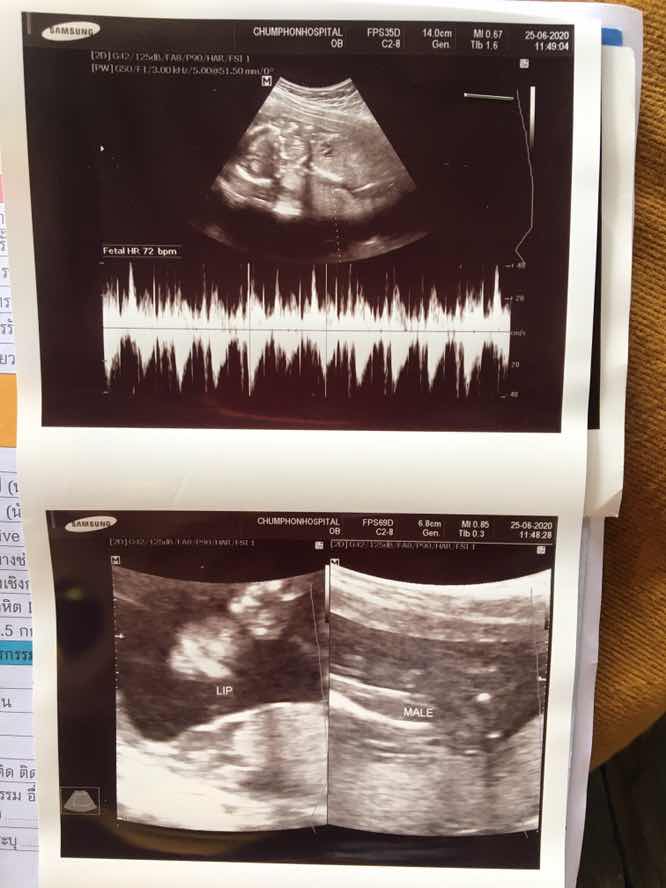

23/11 ชายค่ะ